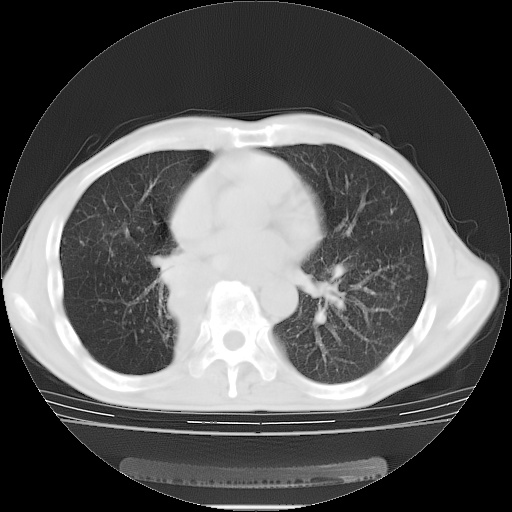

标题: CT15131:M63Y,胸痛2月,加重一周 [打印本页]

男性患者,63岁。右侧胸背部疼痛2月,加重一周。

考虑:右肺中央型肺癌并右肺下叶不张;两肺尖继发性肺结核。

还有纵隔多处肿大淋巴结及肋骨的改变、两肺多发结节灶。

右肺下叶支气管狭窄闭塞,右下肺不张,气管前间隙淋巴结肿大,两上肺散在分部粟粒灶,沿肺血管支气管束分部,血管支气管束走形较为光滑。考虑右肺中心型肺癌合并肺不张,纵隔淋巴结转移,两上肺癌性淋巴管炎

右肺下叶中心性肺癌并纵隔淋巴结转移,左侧肋骨转移。双肺上叶继发性结核表现。

1)右肺下叶中心性肺癌并纵隔淋巴结转移,两肺转移,左侧肋骨转移。2)双肺上叶继发性结核。

右肺下叶中心性肺癌并纵隔淋巴结及两肺、左侧肋骨转移。双肺上叶继发性结核表现。